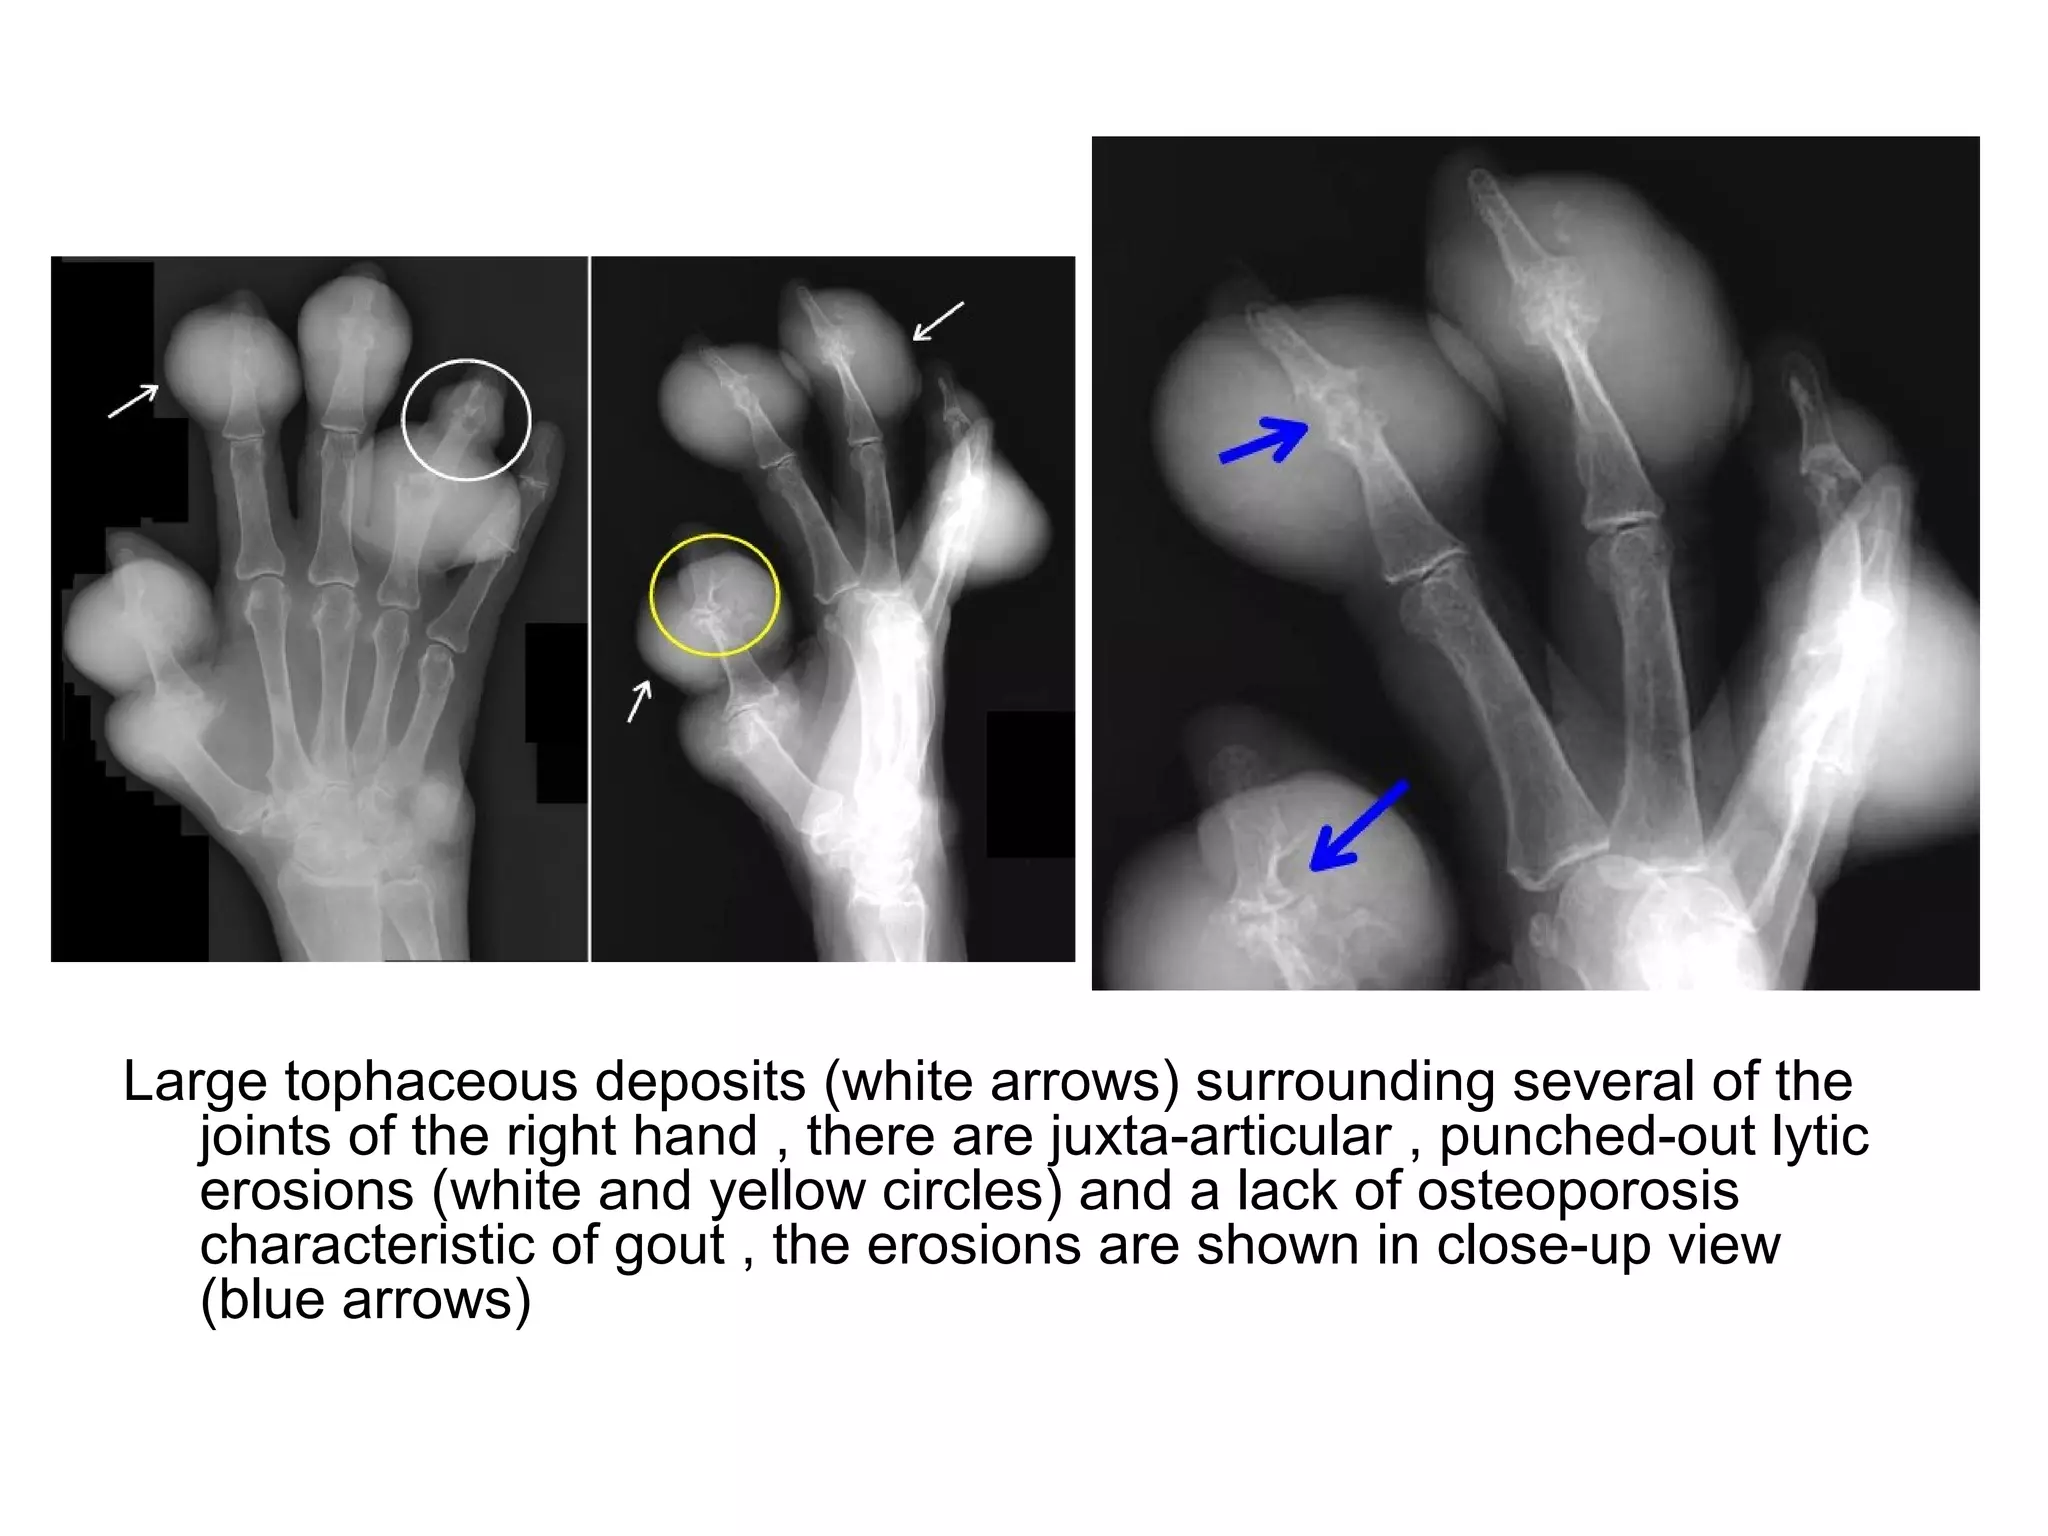

Large tophaceous deposits (white arrows) surrounding several of the

joints of the right hand , there are juxta-articular , punched-out lytic

erosions (white and yellow circles) and a lack of osteoporosis

characteristic of gout , the erosions are shown in close-up view

(blue arrows)